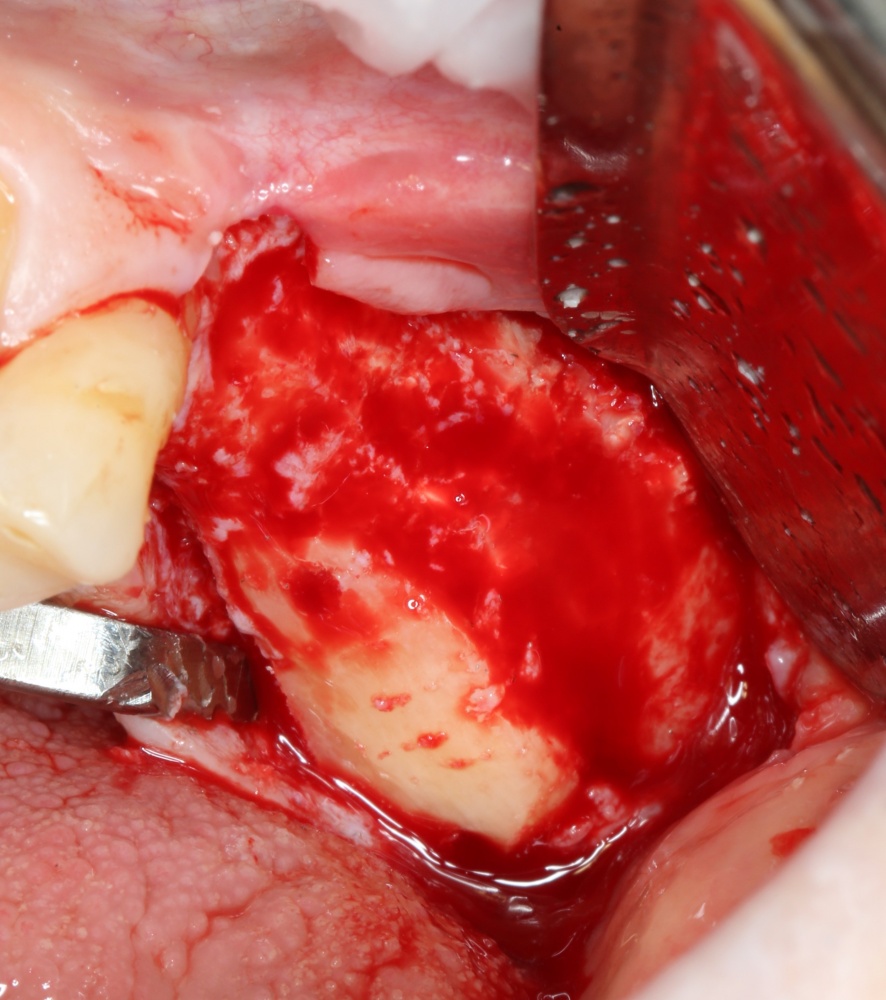

Для получения костного блока, мы открываем донорскую зону, наружную косую линию нижней челюсти.

Получение костного аутотрансплантата.

Здесь потребуется пародонтологический зонд с миллиметровой разметкой или какой-то другой измерительный прибор (операционная линейка). Ранее по КЛКТ я измерил костный дефект, теперь нужно нанести границы будущего костного блока на донорскую зону.

Ремарка: некоторые доктора предлагают делать хирургические шаблоны или выкройки специально для точного забора костного блока. На мой взгляд, это чрезмерное усложнение - во-первых, использование подобных шаблонов или выкроек требует увеличения площади раны, во-вторых, это увеличивает время и стоимость лечения, в-третьих, на этом этапе не требуется высокая точность, поскольку блок всё равно потребует адаптации.

Иными словами, важна не точность, а быстрый, аккуратный и, что главное, малотравматичный забор аутотрансплантата.

Для получения костного блока мы использовали ультразвуковую пьезохирургическую систему. Это самый удобный и безопасный инструмент для проведения подобных манипуляций. С помощью него мы сформировали и выделили костный блок. Он должен отделяться легким движением остеотома или элеватора. Как это сделать правильно — читай здесь>>

Кстати, если костный блок не отделяется от костного ложа легким движением элеватора, значит он неправильно сформирован или не до конца выделен. Вообще, любое чрезмерное усилие в хирургии — это всегда следствие рукожопия. Если тебе что-то приходится делать с усилием (установка имплантата, удаление зуба и т. д.) — значит ты делаешь это неправильно. Остановись и подумай, что именно.